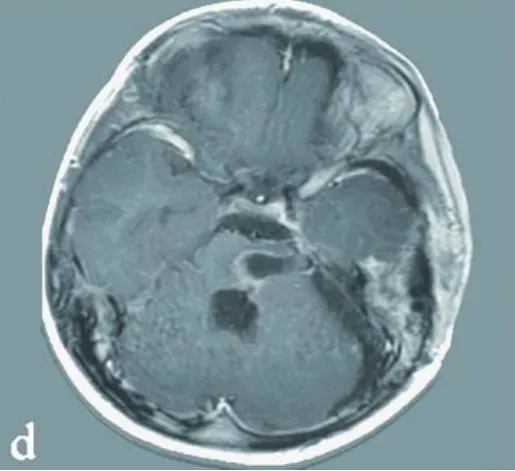

一次突發(fā)的左側肢體無力,讓37歲的中國香港患者佩珊被診斷出腦干橋腦海綿狀血管瘤出血,她的人生也陷入了手術可能會癱與再次出血可能致殘的兩難絕境。 就在這時,一場看似不可能的手術...